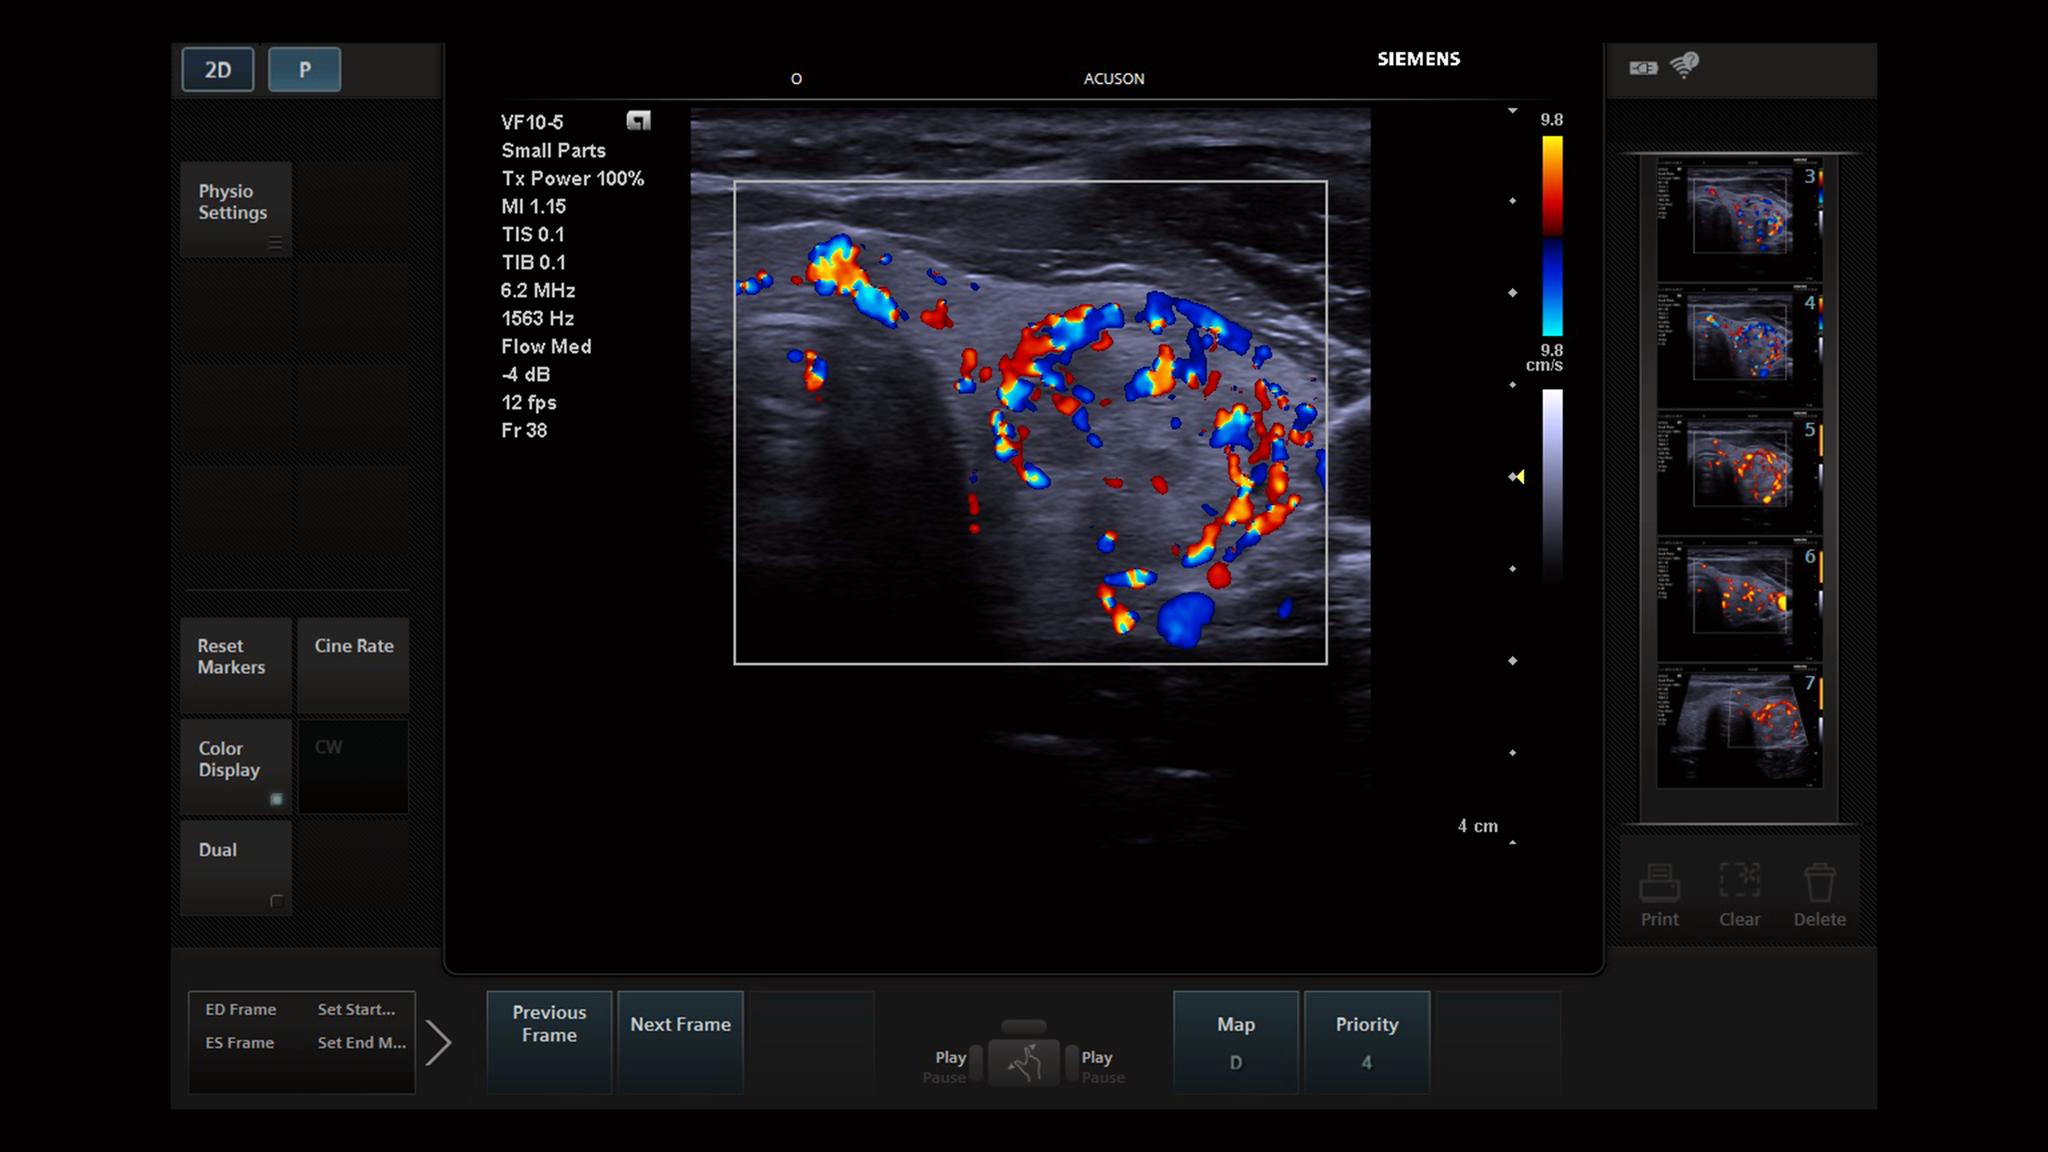

The color flash artifact is a commonly encountered artifact on color Doppler ultrasound, representing spurious flow signal arising due to tissue/transducer motion. Physics The flash artifact is caused by movement of reflective tissues (e.g. due to respiration), or the transducer, which generates a Doppler shift, and thus a color signal 1.

Doppler spectrum displays no true flow Flash artifact Flash artifact occurs as a result of motion of the patient or the transducer and presents as a sudden flash of color filling the color box and obstructing the grayscale image. It can be useful as "color bruit" that presents as a color mosaic in tissue adjacent to a vessel with turbulent. Taking ultrasound to new heightsThe new ACUSON Sequoia is built with unique and patented BioAcoustic Imaging technologies to virtually eliminate color flash architects and penetrate deeper than conventional ultrasound systems.

The color flash artifact is a commonly encountered artifact on color Doppler ultrasound, representing spurious flow signal arising due to tissue/transducer motion. Physics The flash artifact is caused by movement of reflective tissues (e.g. due to respiration), or the transducer, which generates a Doppler shift, and thus a color signal.

Flash artifacts in ultrasound flow images are suppressed to achieve enhanced flow discrimination. Flash artifacts typically occur as region of elevated signal strength (brightness or equivalent color) within an image. A flash suppression algorithm included the steps of estimating the flash within an image and then suppressing the estimated flash.